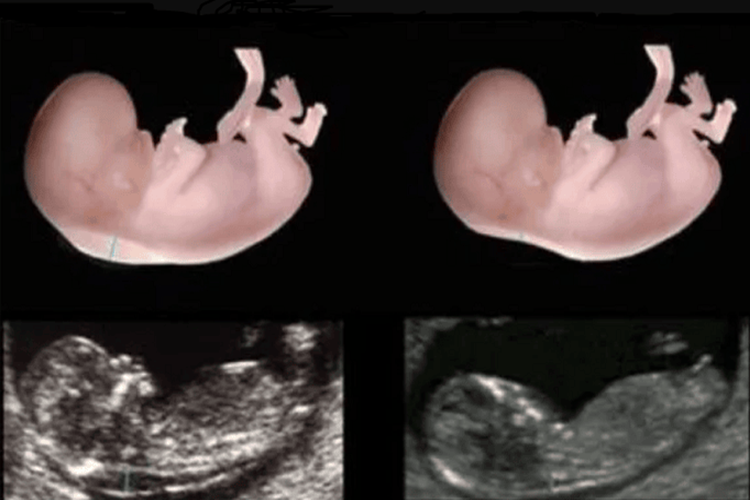

İkili Tarama Testi Kaçıncı Haftada Yapılır?

İkili tarama testi, tipik olarak hamileliğin 11 ila 14. haftaları arasında yapılır. Bu test, genetik anomalileri değerlendirmek için kullanılır ve anne adayının yaşına, bebeğin ultrason tarihine ve kan testi sonuçlarına dayanarak yapılır. Bu test, Down sendromu ve trizomi 18 gibi genetik anormallikleri tespit etmeye yardımcı olabilir. Ancak, net bir tanı koymak için bu testin sonuçları, daha spesifik tanı testleri ile birlikte değerlendirilir. Bu nedenle, hamilelik sürecinde doktorunuzla ikili tarama testi ve diğer tıbbi testler hakkında konuşmak önemlidir.